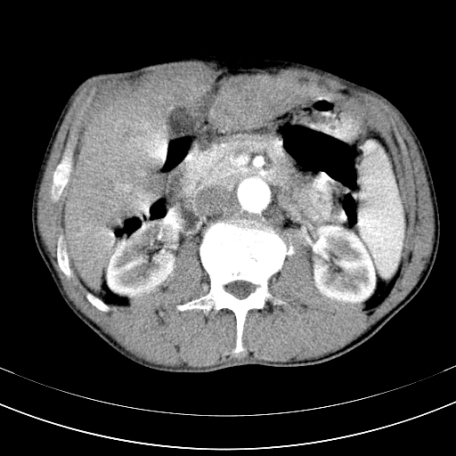

标题: CT21441:男55岁,上腹部胀痛半年余,请老师们看看是后腹膜淋巴 [打印本页]

标题: CT21441:男55岁,上腹部胀痛半年余,请老师们看看是后腹膜淋巴

腹主动脉右侧有一个,有肿瘤病史吗?

腹膜后淋巴结肿大,原因待查。